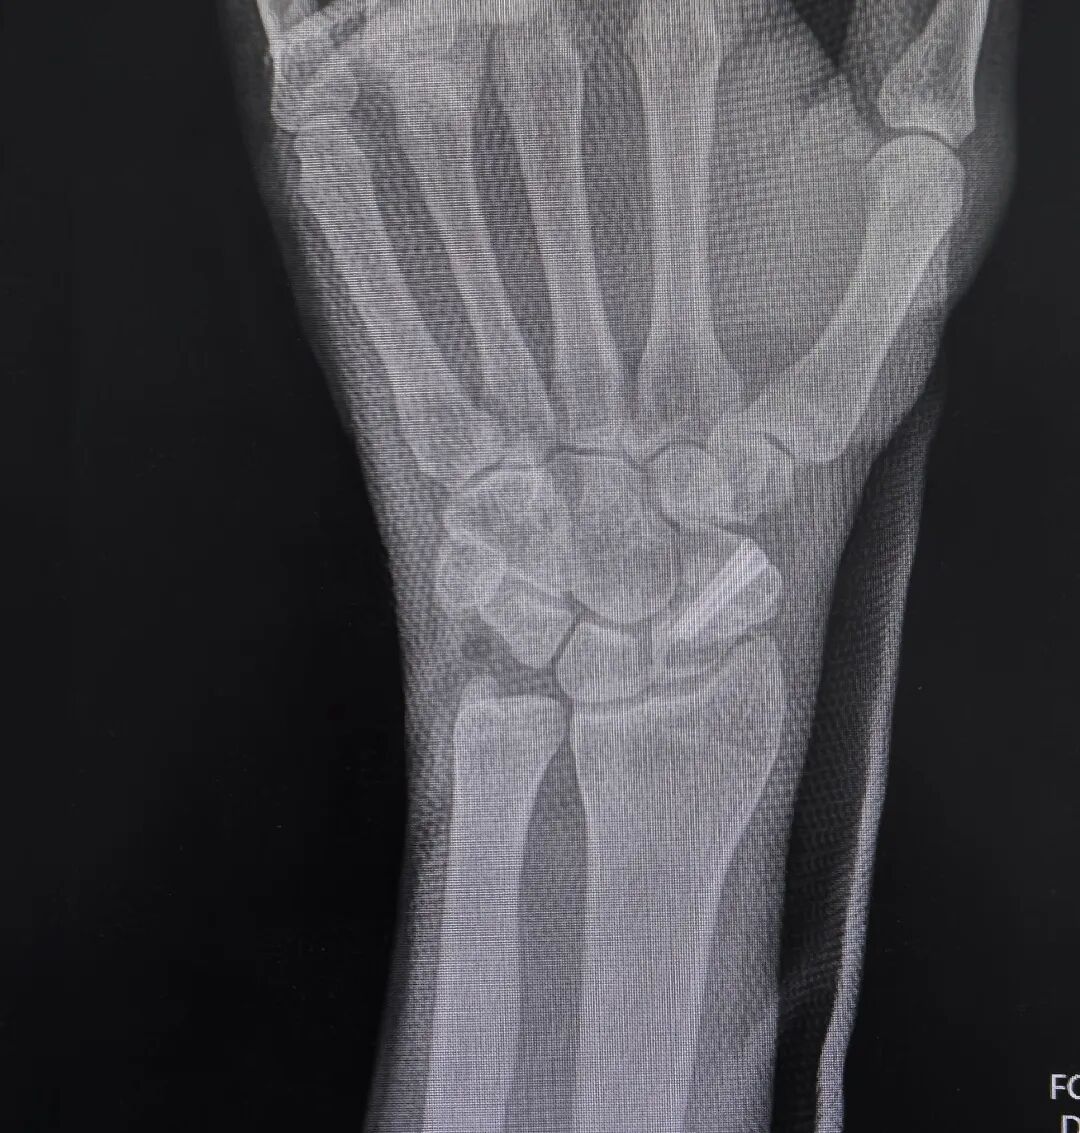

郭阳院长仔细翻阅他 20 多年来的病历,结合最新的检查结果,指着影像片上的病灶,耐心解释:“你这是典型的陈旧性舟骨骨不连,骨折端已经硬化、萎缩,周围腕关节也出现了代偿性磨损,普通手术很难彻底清理硬化骨、稳定固定,容易再次不连,需要植骨重建 + 内固定技术,才能从根源上解决疼痛,恢复腕关节功能。”

手术过程中,发现骨折断端磨损的非常厉害,已经形成了假关节,凭借积水潭手外科精湛的显微操作技术,郭阳院长精准定位骨折部位,细致清理硬化骨组织,取自体尺骨鹰嘴骨植入骨缺损区,再用螺钉牢固固定,一步步为陈先生重建了健康的腕关节结构。

术后复查的 X 线片上,曾经断裂、硬化的舟骨被稳稳复位,植骨块位置良好。